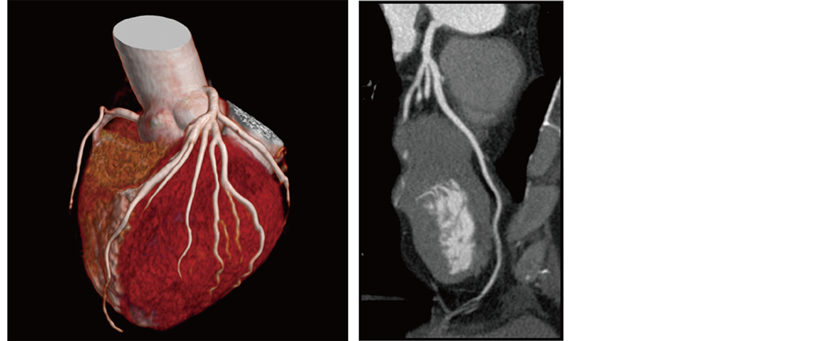

IntelliEC Cardiac reduces dose using electrocardiogram information. Dose modulation can be applied to minimize tube current during non-target phases, including resting phases of mid-diastole and end-systole.

Reconstructed cardiac phase 75%

CardioHarmony enhances cardiac CT workflow by automatically*6 detecting and reconstructing cardiac phases with minimal motion.

- *6 The automatic selection must be checked and the operator may adjust, if necessary.